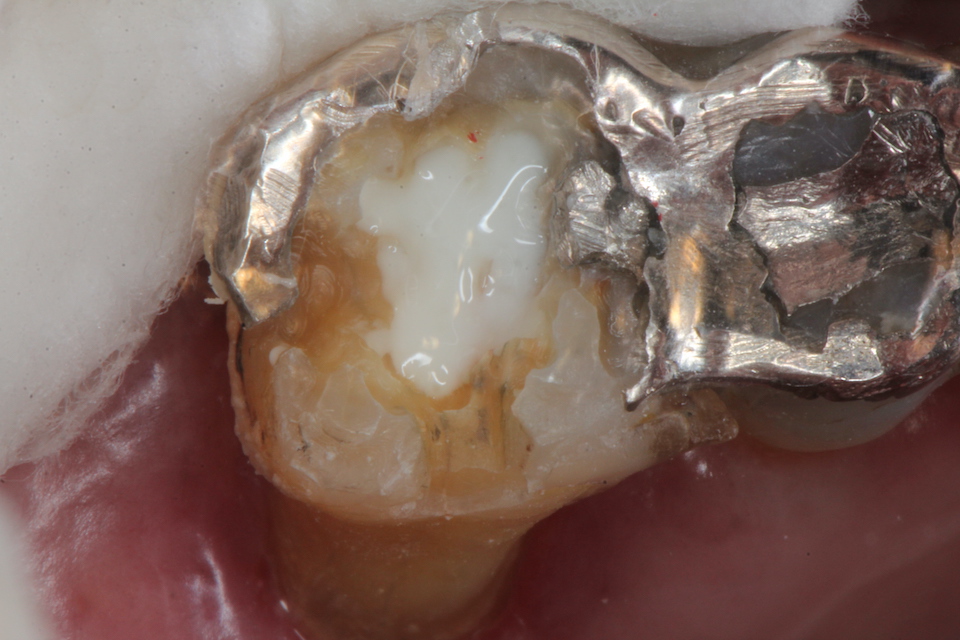

ボスミン液で止血した後は3MIX+α-TCPで根管充填というか直接覆髄というのか、露出している歯髄と根管内を覆うというか注入すればよい。それも緊密充填である必要もない。人間の歯髄というものは非常に丈夫なので炎症があれば全部取る必要があるというのは、これも嘘だ。

α-TCPで充填